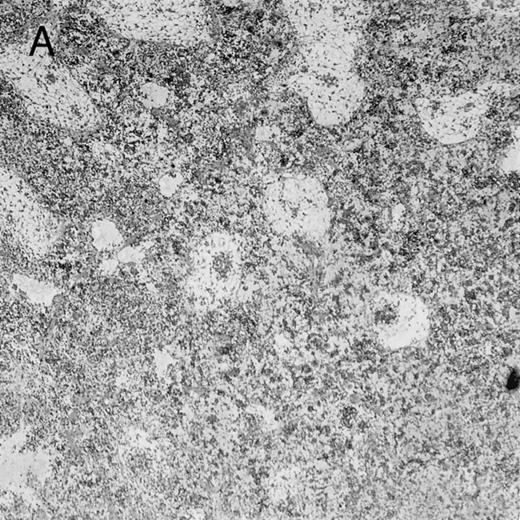

Histologic findings. Organs were collected at different times after BMT and tissue sections were stained with hematoxylin and eosin. Original magnifications for spleen (left) and liver (right) are ×40 and ×100, respectively. (A) B6 mice receiving FVB BM plus EpTK T cells. (B) Control group receiving BM only.

FVB BM-grafted B6 mice: a model of lethal GVHD.We developed a model of GVHD resulting in 100% mortality soon after BMT using FVB mice, a strain not previously used as BM donors in experimental allogeneic BMT. We tested different combinations of recipient irradiation doses, as well as injected BM cell and CD3+ peripheral T-cell numbers. When 10-Gy–irradiated B6 mice were reconstituted with 107 FVB BM cells, we observed prolonged survival, whereas all ungrafted animals died before day 16 (Fig 2). In these conditions, more than 98% of splenocytes were of donor origin (Fig 3A). When 107 CD3+ peripheral T cells from mice of FVB genetic background were added to the FVB BMT, all animals died of GVHD between days 7 and 34 (Fig 2). Similar results were obtained using either PBS-treated mice receiving EpTK or EpΔTK peripheral T cells or GCV-treated mice receiving FVB nontransgenic peripheral T cells. Notably, this observation also indicates that both TK- and ΔTK-expressing T cells in the absence of GCV are fully competent to induce a lethal GVHD. Histopathologic examination of spleen and liver of these animals showed characteristic GVHD lesions such as (1) architecture disruption, necrosis, and congestion in the spleen; (2) hepatic periportal necrosis; (3) mononuclear portal infiltrates; and (4) endothelialitis of portal or centrolobular veinules (Fig 4A). By comparison, B6 mice receiving only FVB BM had a normal histology (Fig 4B).